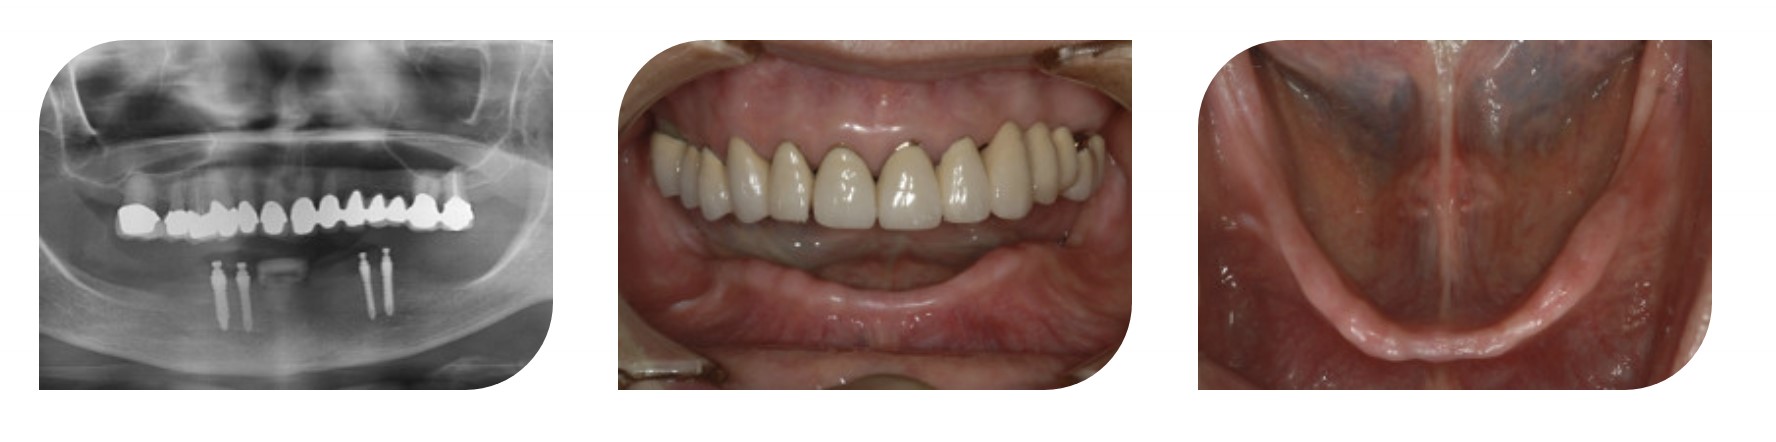

Состояние пациента: беззубая нижняя челюсть

Продукт: Имплантат для съемного протеза MS

Параметры: Φ 2.5 * 13 мм * 2, Φ 3.0 * 13 мм * 2

Панорамный снимок и фотография ротовой полости